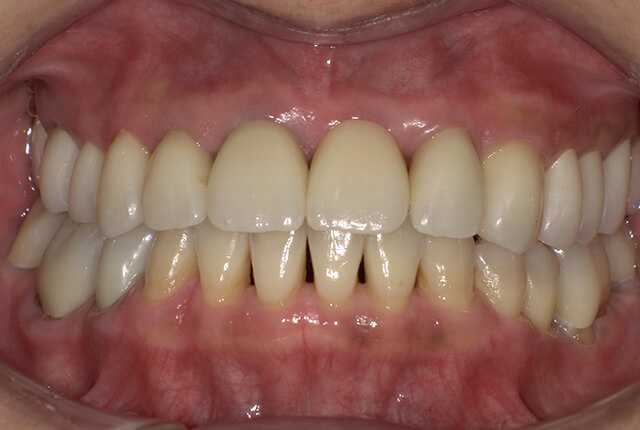

90分の治療で銀歯の状態からキレイな状態になります。噛み合わせの調整や審美面も使用しながら合わせます。

良く噛めて安心と、ご満足いただき大変嬉しく思います。笑顔も一層素敵になりました。

| 治療内容 | 欠損部インプラント 不正咬合に対し不良補綴のやり直しと合わせて咬合再構築 |

| 治療計画 | 欠損部インプラント 不良補綴のやり直しと欠損部インプラント。 咬合の再構築、なるべく歯を残せる様に治療計画を立案。 |